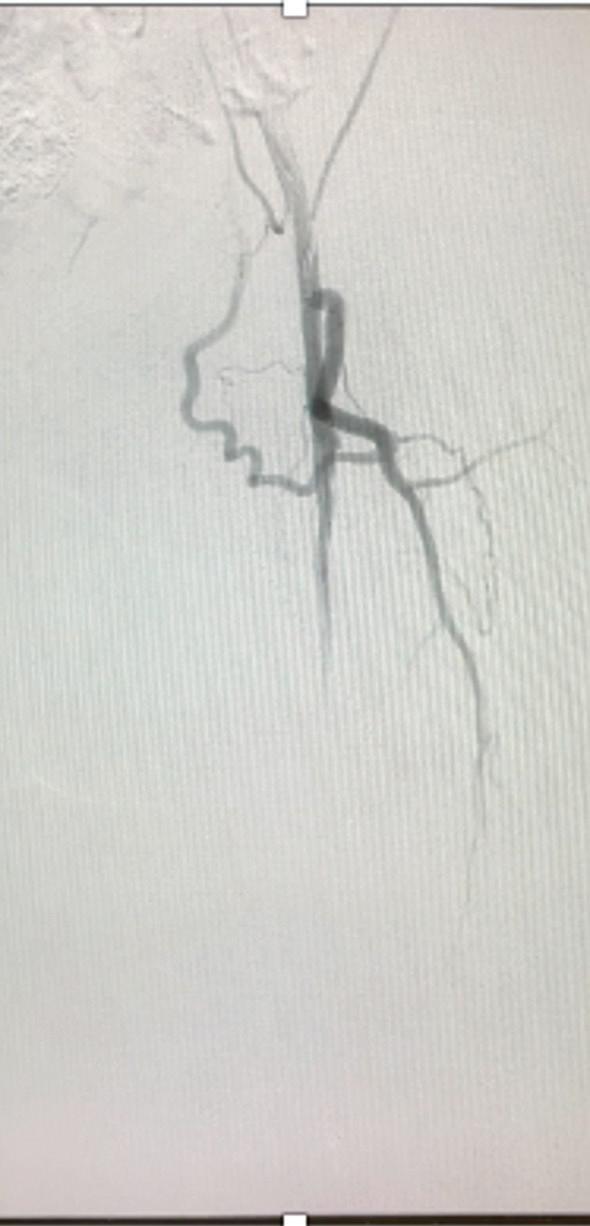

Arteriogram, left lower extremity

An arteriogram of the left lower extremity was performed via antegrade left common femoral artery access based on preoperative review of the lower extremity arteriogram from Uzbekistan. Scattered non-calcified plaque with moderate to high-grade stenoses were identified in the proximal and mid superficial femoral artery. Diffuse severe calcified tibial artery disease was identified. There was a long segment stenosis of the proximal and mid posterior tibial artery coupled with a more distal occlusion. The proximal peroneal artery was calcified and occluded with distal reconstitution identified. There was complete occlusion of the anterior tibial artery (Figure 2).